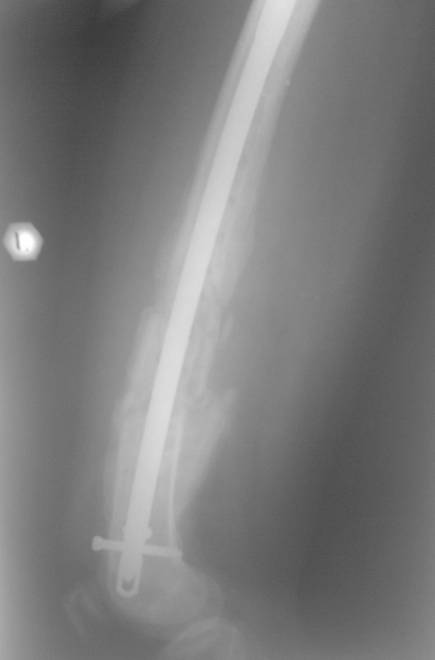

Травма в декабре 2006 года. Диагноз: Сочетанная травма. ЗЧМТ. Ушиб мозга. Кома. Закр. перелом левой плечевой кости; левой лучевой кости; оск. перелом левой бедренной кости.

Оперирована в январе 2007 года по выходе из комы и восстановления витальных функций. Накостный остеосинтез DCP-LC. Снимки прилагаются.

Через 4 месяца стали беспокоить боли и деформация бедра. На снимке угловая деформация AP - варус 11 град.; lateral - 29 град. Объем движений в коленном суставе: ограничение сгибания до 90 град. Локально - патологическая подвижность в нижней трети бедра. Локальная гипертермия, отек мягких тканей. Гиперемии нет. Передвигалась на костылях.

В мае 2007 года оперирована в Уральском НИИТО г. Екатеринбурга. Выполнено: полузакрытое удаление пластины и винтов, IM блокируемый остеосинтез.

На сегодняшний момент (2 месяца после операции). Больная передвигается при помощи трости из-за чувства неуверенности и ощущения онемения в подколенной ямке. В квартире передвигается без дополнительной опоры. Снимки в аттаче.

1. Удалять ли статический винт? Сроки? Способ?

2. Причины и возможные методы лечения индуративного отека н/3 бедра?